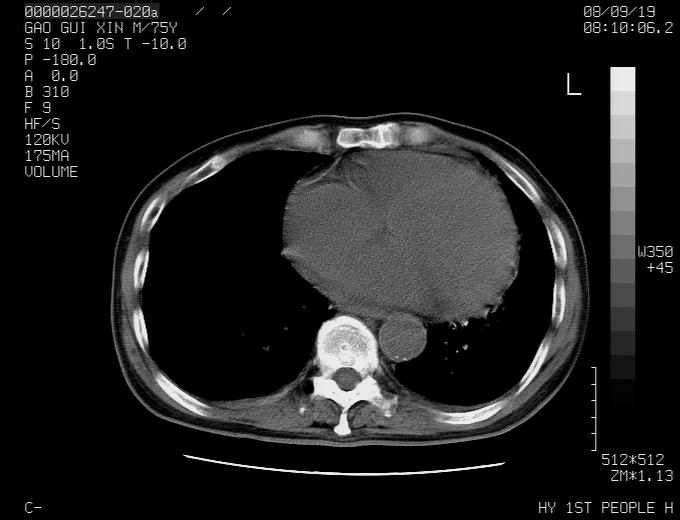

感谢各位老师的意见,左上肺病灶,我本人趋向结核,原因:左上肺见两个类圆形结节,仔细回顾4月份ct似乎原片在该处有条片状密度增高影,强化不明显。

现上传增强片,请各位老师仔细帮我看一下。

右上肺可见条索状影,并可见钙化,左上肺结节可以考虑为结核球,但气管前腔静脉后有肿大淋巴结,本人觉得左上肺结节不能排除转移瘤的可能,右上肺为陈旧性结核灶。

左肺上叶周围性肺癌并纵隔多组lnm.不可能是tb.

左肺上叶尖段瘢痕癌并纵隔淋巴结转移解释更好一些.

双上肺继发型肺结核,纵隔淋巴结结核可能性大,建议定期复查.

左肺周围癌并纵隔淋巴结转移,另一小结节是血管影

别再ct讨论了,一个纤支镜检查马上明确.肺癌不会错的!应该是低分化鳞癌.

左上肺周围型肺癌并纵隔淋巴结转移

1)左肺上叶尖段周围型肺癌并纵隔淋巴结转移。2)冠状动脉及主动脉钙化。

左上肺周围型肺癌并纵隔淋巴结转移。纤支镜检查